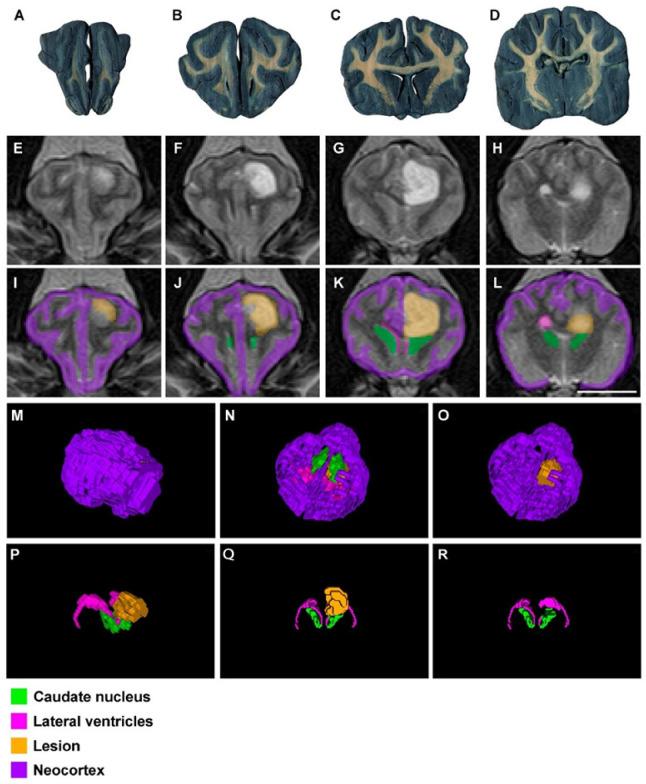

Neuroanatomy is always a challenging topic for veterinary students. It is widely accepted that understanding the anatomy of the central nervous system (CNS) is essential to explain many of the pathological processes that affect the brain. Although its study has varied over time to achieve this goal, in human and veterinary medicine it is difficult to find a teaching method that associates normal anatomy with pathological alterations of the brain. For the first time, we have created an educational tool that combines neuroanatomy and neuropathology, using different magnetic resonance (MR) images as a basis and EspINA software as analyzer, to obtain segmented structures and 3D reconstructions of the dog brain. We demonstrate that this combination is an optimal tool to help anatomists to understand the encephalon, and additionally to help clinicians to recognize illness including a multitude of neurological problems. In addition, we have tried to see whether photogrammetry, which is a common technique in other sciences, for example geology, could be useful to teach veterinary neuroanatomy. Although we still need further investigations, we have been able to generate 3D reconstructions of the whole brain, with very promising results to date.

神经解剖学对兽医专业的学生来说一直是个具有挑战性的课题。人们普遍认为,了解中枢神经系统(CNS)的解剖结构对于解释许多影响大脑的病理过程至关重要。尽管为实现这一目标,其研究方法随时间有所变化,但在人类医学和兽医学中,很难找到一种能将正常解剖结构与大脑病理改变联系起来的教学方法。我们首次创建了一种教育工具,它以不同的磁共振(MR)图像为基础,以EspINA软件为分析器,将神经解剖学和神经病理学结合起来,以获取犬脑的分割结构和三维重建。我们证明,这种结合是帮助解剖学家理解脑,以及帮助临床医生识别包括多种神经问题在内的疾病的最佳工具。此外,我们还尝试探究摄影测量法(这在其他科学领域,如地质学中是一种常用技术)是否有助于兽医神经解剖学的教学。尽管我们仍需进一步研究,但到目前为止,我们已经能够生成全脑的三维重建,结果很有前景。